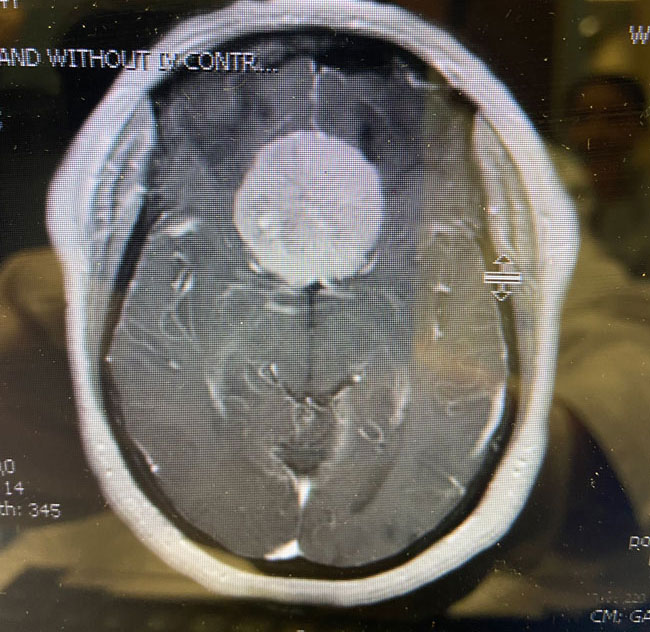

This is a 64 year-old woman with no significant past medical history who noted rapid deterioration of vision in her left eye 3 weeks earlier. She said it felt like there was a cloud over her eye. Ophthalmology evaluation confirmed poor vision in the left eye and ordered a brain MRI. The MRI demonstrated a large planum sphenoidale meningioma with significant compression on the optic nerves and optic chiasm and significant surrounding edema (Figures 1 a, b, and c). She was then referred to Dr. Michael Brisman for neurosurgical evaluation.

If this tumor were smaller, causing less edema, and no symptoms, it might well have been possible to treat it with stereotactic radiosurgery alone. However, because of the large size, the significant surrounding edema, and the rapid progression of symptoms, it was felt that this was a patient best managed with open surgery. The significant amount of brain edema is expected to completely resolve. The small remaining piece of tumor may be treated at a later date with stereotactic radiosurgery.